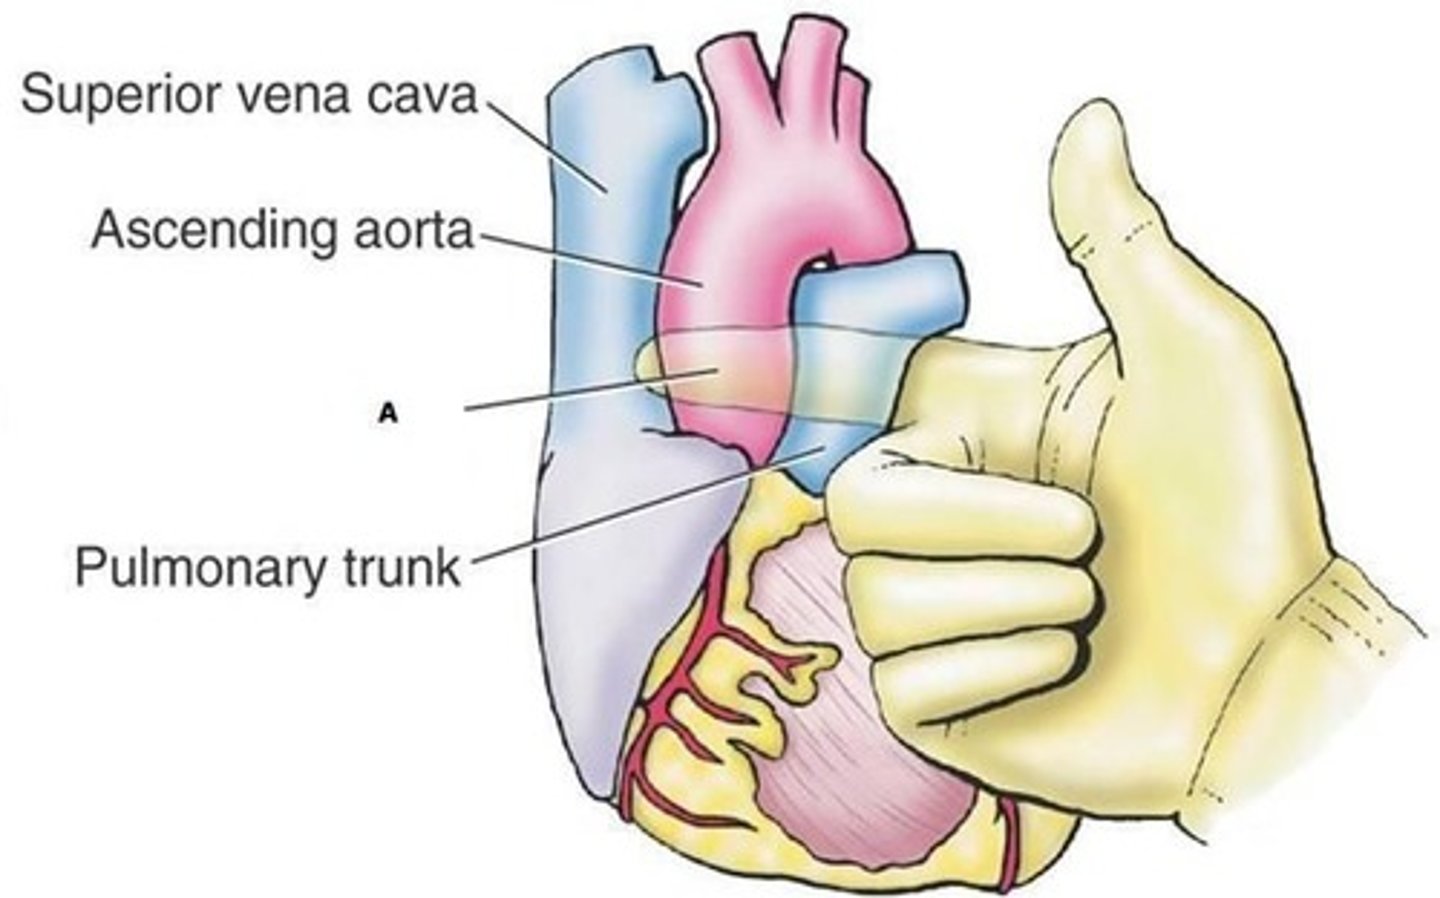

Jakie duże naczynia wychodzą z serca? Skąd dokładnie?

aorta wstępująca z komory lewej

pień płucny z komory prawej

Jak jest położone serce?

asymetrycznie, bardziej po lewej

Jak biegnie oś serca?

od przodu, dołu i lewej strony

do tyłu, góry i prawej strony

Jak zrotowane jest serce?

komora prawa jest najbardziej z przodu

komora lewa z lewej strony

przedsionek prawy po prawej stronie

przedsionek lewy z tyłu